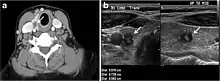

Fig. 1. An incidentally discovered colloid nodule with calcification, shown on CT scan of a 58-year-old female patient. a Non-enhanced axial CT scan of the neck demonstrates a coarse calcification at the left thyroid inferior pole. b Sagittal grey scale ultrasound of the thyroid demonstrates a heterogeneous nodule with a predominant cystic component. Calcification was not seen in the ultrasound, probably due to its lower location in the superior mediastinum.[1]

Fig. 2. A 51-year-old female patient post left hemithyroidectomy, with incidentally discovered a right thyroid colloid nodule on CT scan. an Enhanced axial CT scan of the neck demonstrates a well-defined, hypodense right thyroid nodule (white arrow) with no internal calcifications or cervical lymphadenopathy. b Transverse greyscale thyroid ultrasound demonstrates a well-defined, hypoechoic right thyroid lobe nodule with a central echogenicity including comet tail (ring down) artefacts (white arrow). No vascularity (not shown) or calcifications were detected.